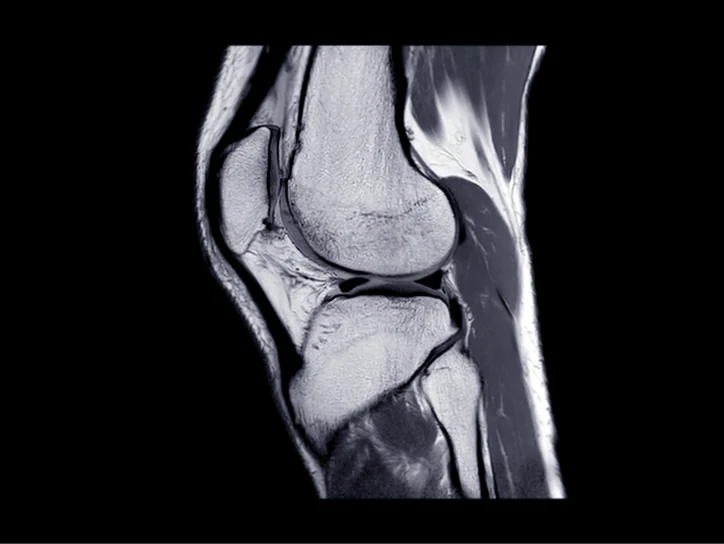

MRI scan of knee joint used for diagnosis.

3. Imaging Tests – X-rays, MRI, and ultrasound are used to assess the structure and condition of the knee, providing insights for diagnosis and treatment planning.